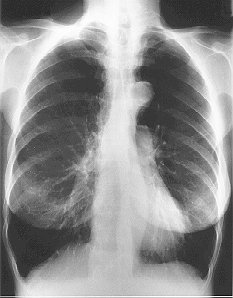

The presence emphysema can be suspected on routine chest radiography but this is not a sensitive technique for diagnosis. Large volume lungs with a narrow mediastinum and flat diaphragms are the typical appearances of emphysema Fig.8). In addition, the presence of bullae and irregular distribution of the lung vasculature may be present. In more advanced disease, the presence of pulmonary hypertension may be suspected by the prominence of hilar vasculature. The chest X-ray is not a very good indicator of the severity of disease and will not be able to identify patients with COPD without significant emphysema. However, the chest X-ray is useful to look for complications during acute exacerbations and to exclude other pathology such as lung cancer.

Fig. 8: Typical CXR of emphysema